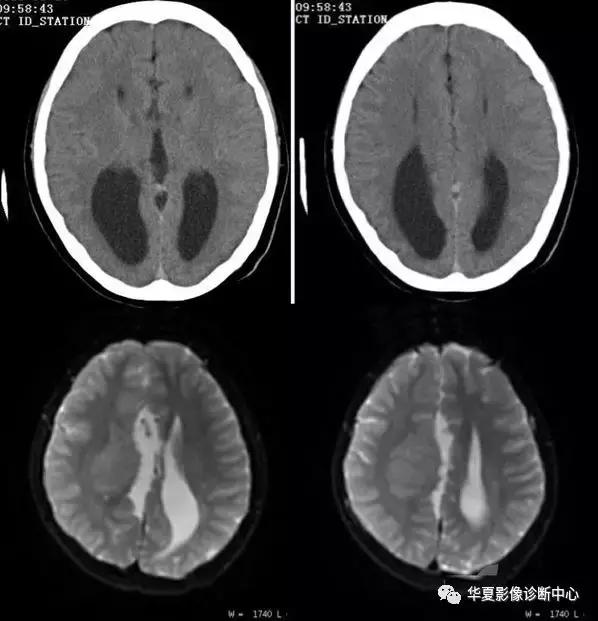

七、反转征:

儿童弥漫性脑白质和灰质的密度减低、伴有灰白质界限不清或消失,或灰白质密度反转,而丘脑、脑干和小脑密度相对增高根据“反转征”出现时间分急性和慢性2期。急性指当时CT扫描即有“反转征”,慢性为弥漫性脑萎缩/脑软化伴“反转征”。急性期神经病理学改变主要为大脑皮质和白质发生急性神经元坏死和脑水肿,脑干及丘脑淤点状出血。Baenziter等认为缺氧缺血后大脑皮层第Ⅲ、Ⅳ层神经细胞最易受损,缺血后12小时以上大脑皮层神经细胞即发生嗜酸样变性,基质发生凝固性坏死,2~3 天轴索开始变性,7天左右出现成胶质细胞、脂肪颗粒和新生血管,2~4周形成空洞和软化,进一步论述了缺氧缺血后皮层神经细胞的病理过程。基底节和丘脑损害所发生的密度增高目前有几种认识:国内学者认为系缺氧后上述区域发生大理石样变性所致,表现为神经元的丧失、星形细胞胶样变性及髓鞘过度形成,尤其壳核背外侧与丘脑腹外侧髓鞘化最活跃,需氧量最高,代谢旺盛,对缺氧缺血敏感,因此受累也最为严重。有的则认为是严重缺血后1~2周新生毛细血管网的大量增加或与大脑的白质深部髓质静脉扩张淤血有关,甚至有人认为不是密度增高,而是正常脑组织密度。这种密度增高是相对的,虽然在急性期脑中央区域的密度增高个体间存在一定的密度差异,但本组从未见有像脑血管破裂出血那样的高密度,CT值多在22 HU左右,因此这种密度增高是相对的。

“反转征”的分期,急性期应以生后当时CT扫描结果为准。一般来说,生后3天多以脑水肿为主,其后为脑实质缺氧缺血性损害,所以生后5~10 天扫描较为可靠。慢性期以生后3~8周为妥,此期已出现明显脑软化、脑萎缩,脑实质密度明显低于急性期。急性“反转征”的患儿需要呼吸支持和重症监护,延误治疗者可转变为慢性“反转征”,其密度变化更具有特征性。有人认为重症病人在3个月时即可发生脑软化和脑萎缩,发生率约占HIE病例的20%。与此同时,丘脑与脑干的密度增高较急性期更加显著,如同“增强”一样,CT值22~26 HU,丘脑形态轮廓勾画清楚,犹如雪山的“山丘”,出现这种明显反差的影像学表现可能与脑软化的低密度衬托有关,若不仔细的观察和测量CT值易误为脑出血。

“反转征”主要发生在重度HIE病例中,因此“反转征”可视为重度HIE少见而重要的征象,可把它作为HIE诊断及分级和评价预后的重要依据。

CT“反转征”是新生儿重度缺氧缺血性脑损伤的一种重要CT征象,但并非特异性,也可以在某些疾病中如外伤(虐待伤)、病毒性脑炎等出现。特别应注意慢性“反转征”与HIE的并发症鉴别。众所周知,HIE常见并发症为外部性脑积水和局限性脑软化灶和脑萎缩,前者不存在鉴别问题,后者CT上脑软化灶多发生在顶枕叶或双侧脑室旁白质内,多为局限性,而慢性“反转征”则表现为半球弥漫性低密度区,同时基底节及丘脑等脑中央区域密度增高明显,表现特殊,这点对鉴别诊断有相当重要的价值。因此,重度窒息儿大脑灰白质密度弥漫性减低伴灰白质界限消失或密度反转以及基底节、丘脑、脑干和小脑密度相对增高是重度HIE的特征性CT表现,是诊断急、慢性CT“反转征”的重要依据。急性期脑室受压变窄和慢性期脑室扩大主要与脑水肿和脑软化/脑萎缩有关。“反转征”一旦出现,高度提示脑组织有不可逆性脑损伤存在,预后大多不良,即使存活也将发生脑瘫或智力障碍等后遗症。